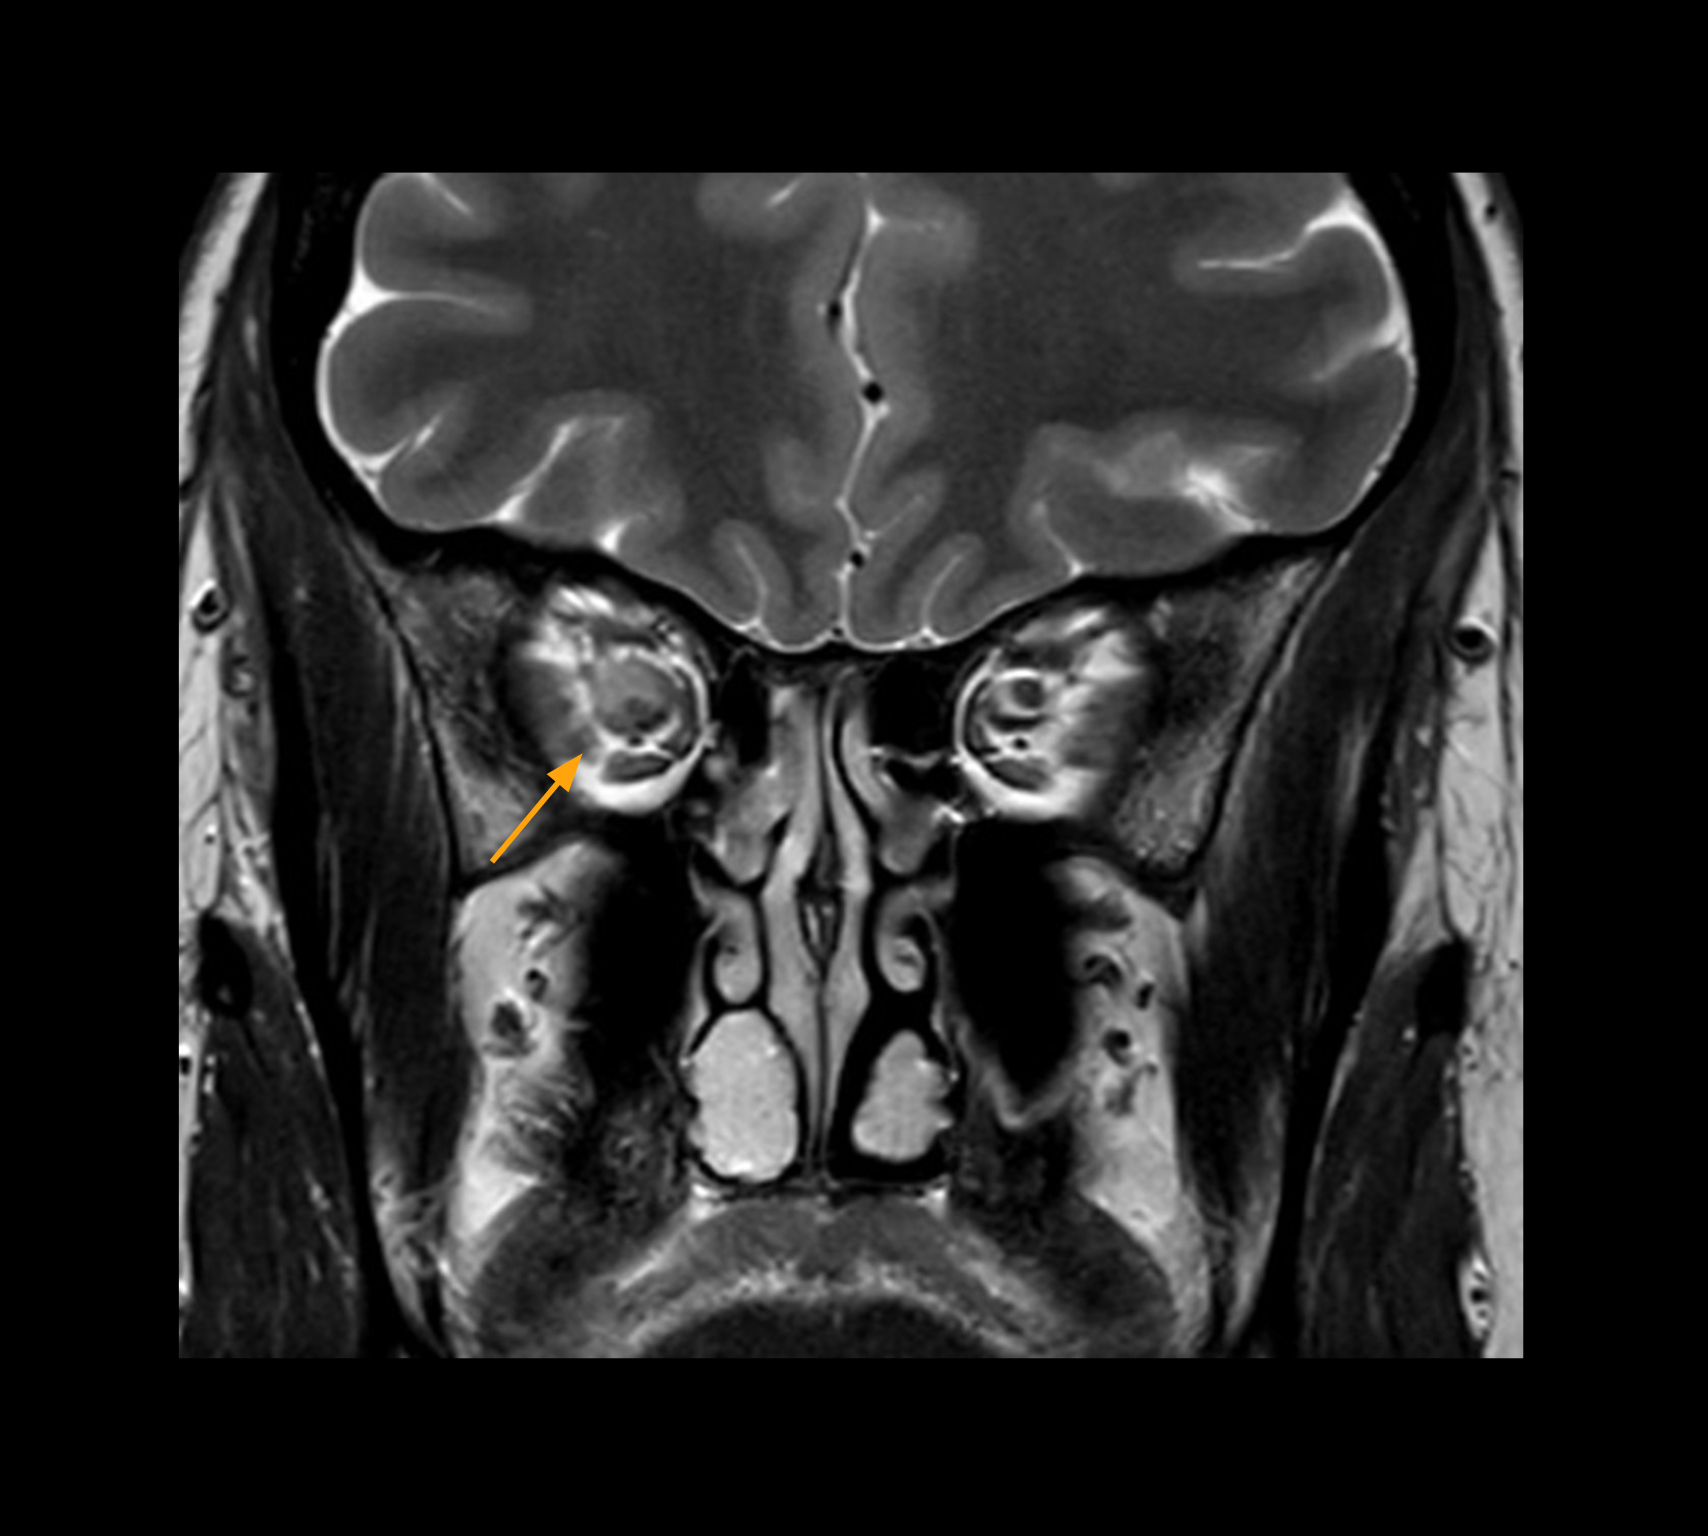

Imaging of the optic nerve sheath

High-resolution MRI impressively demonstrates the compression and narrowing of the right optic nerve in this case of optic nerve sheath meningioma (ONSM). The coronal T2-weighted images show the hyper-intense, half-moon shaped lesion, that is clearly visible in the axial T1W image after contrast injection (right). These imaging findings were so convincing that there sponsible neurosurgeon did not consider a pretherapeutic histological clarification.

Imaging of the optic nerve sheath

High resolution-MRI impressively demonstrates the compression and narrowing of the right optic nerve in this case of optic nerve sheath meningioma (ONSM). The coronal T2-weighted images show the hyper-intense, half-moon shaped lesion, that is clearly visible in the axial T1W image after contrast injection (right). These imaging findings were so convincing that there sponsible neurosurgeon did not consider a pretherapeutic histological clarification.